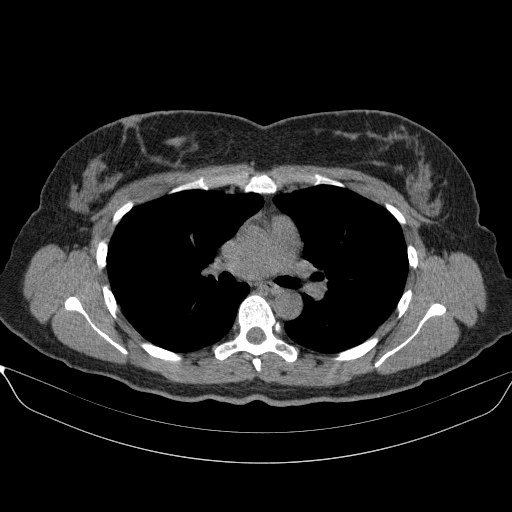

Image Grid

4Γ—3 grid: Rows show different image types (Original NATIVE, Reconstructed NATIVE, Original VENOUS, Generated VENOUS), Columns show windowing techniques (No Window, Lung Window, Mediastinum Window)

Reconstructed NATIVE CT scan (cycle consistency)

Mediastinum window (WL 40, WW 400 β†’ Low βˆ’160, High +240)

Original VENOUS CT scan

Generated VENOUS CT scan (A→B translation)